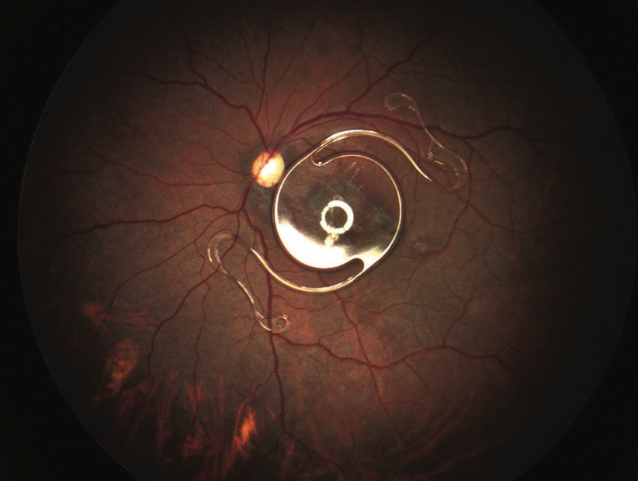

眼底照片显示黄斑区可见瘢痕,可能与先前所受钝挫伤有关;玻璃体腔后极部可见Kelman Multiflex型前房人工晶状体自由移动。(见图2)

图2. 黄斑区瘢痕;后极部人工晶状体自由移动